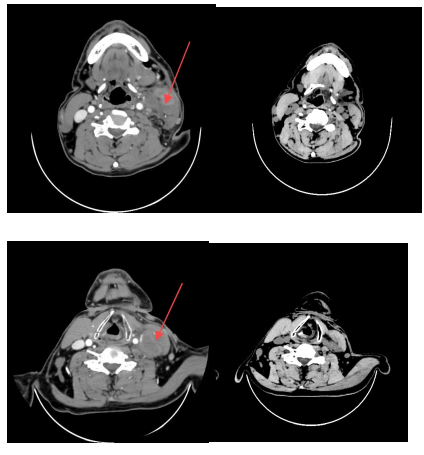

(一)鼻咽癌

治疗前CT显示鼻腔、颈部肿块明显,经调强放射治疗33次后1个月复查,肿块显著缩小,患者病情得到有效控制。